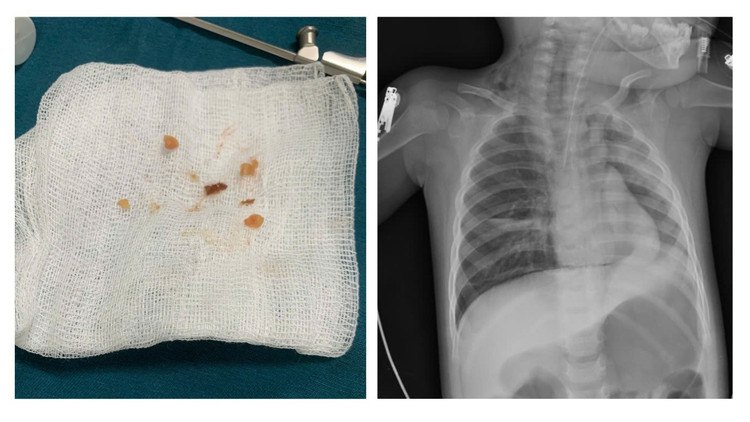

Để cứu bệnh nhi, Bệnh viện Sản nhi Quảng Ninh đã triển khai quy trình báo động đỏ, quy trình phối hợp hội chẩn - cấp cứu liên viện giữa bệnh viện với ê-kíp Bệnh viện Nhi Trung ương do BSCKII Lê Thanh Chương, Phó Giám đốc Trung tâm Hô hấp, Bệnh viện Nhi Trung ương làm trưởng nhóm. Ê-kíp trực tiếp có mặt phối hợp, sử dụng các dụng cụ chuyên dụng để nội soi và cẩn trọng gắp các dị vật lọt sâu trong đường thở cho trẻ.

keo-lac-3.jpg

Sử dụng dụng cụ nội soi để lấy dị vật ra.